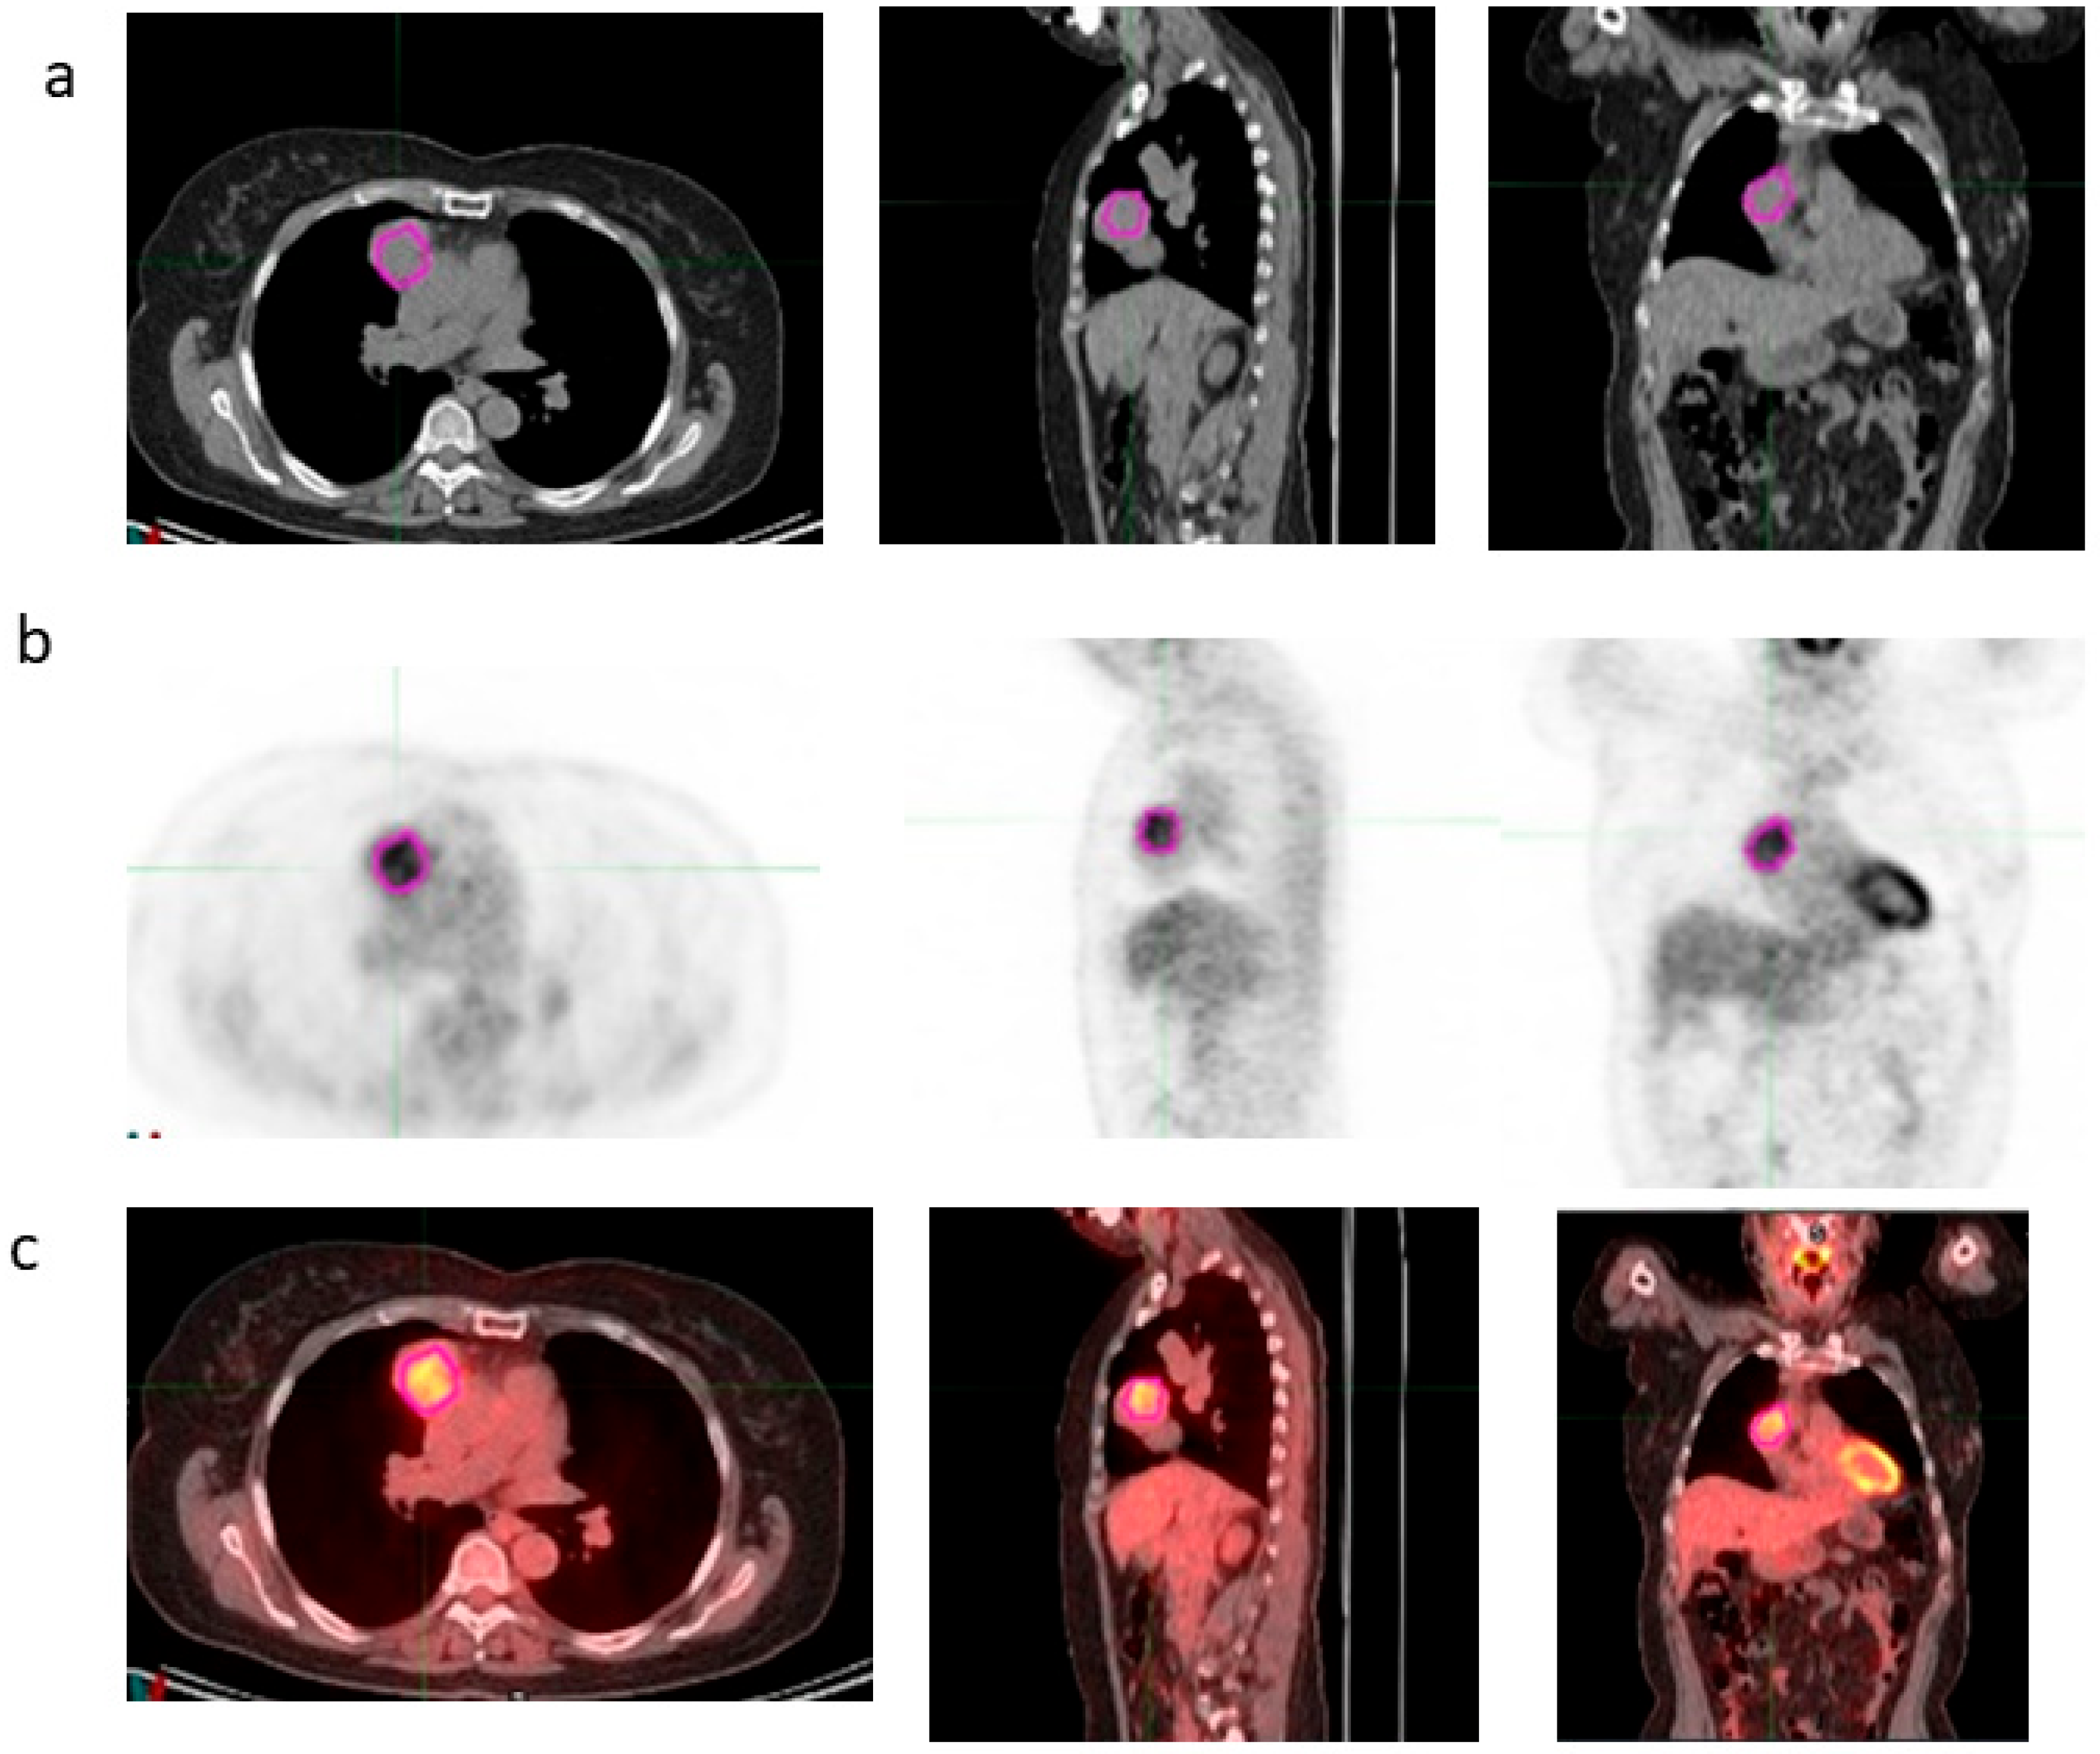

2.4. Imaging Post-Processing and Features Extraction